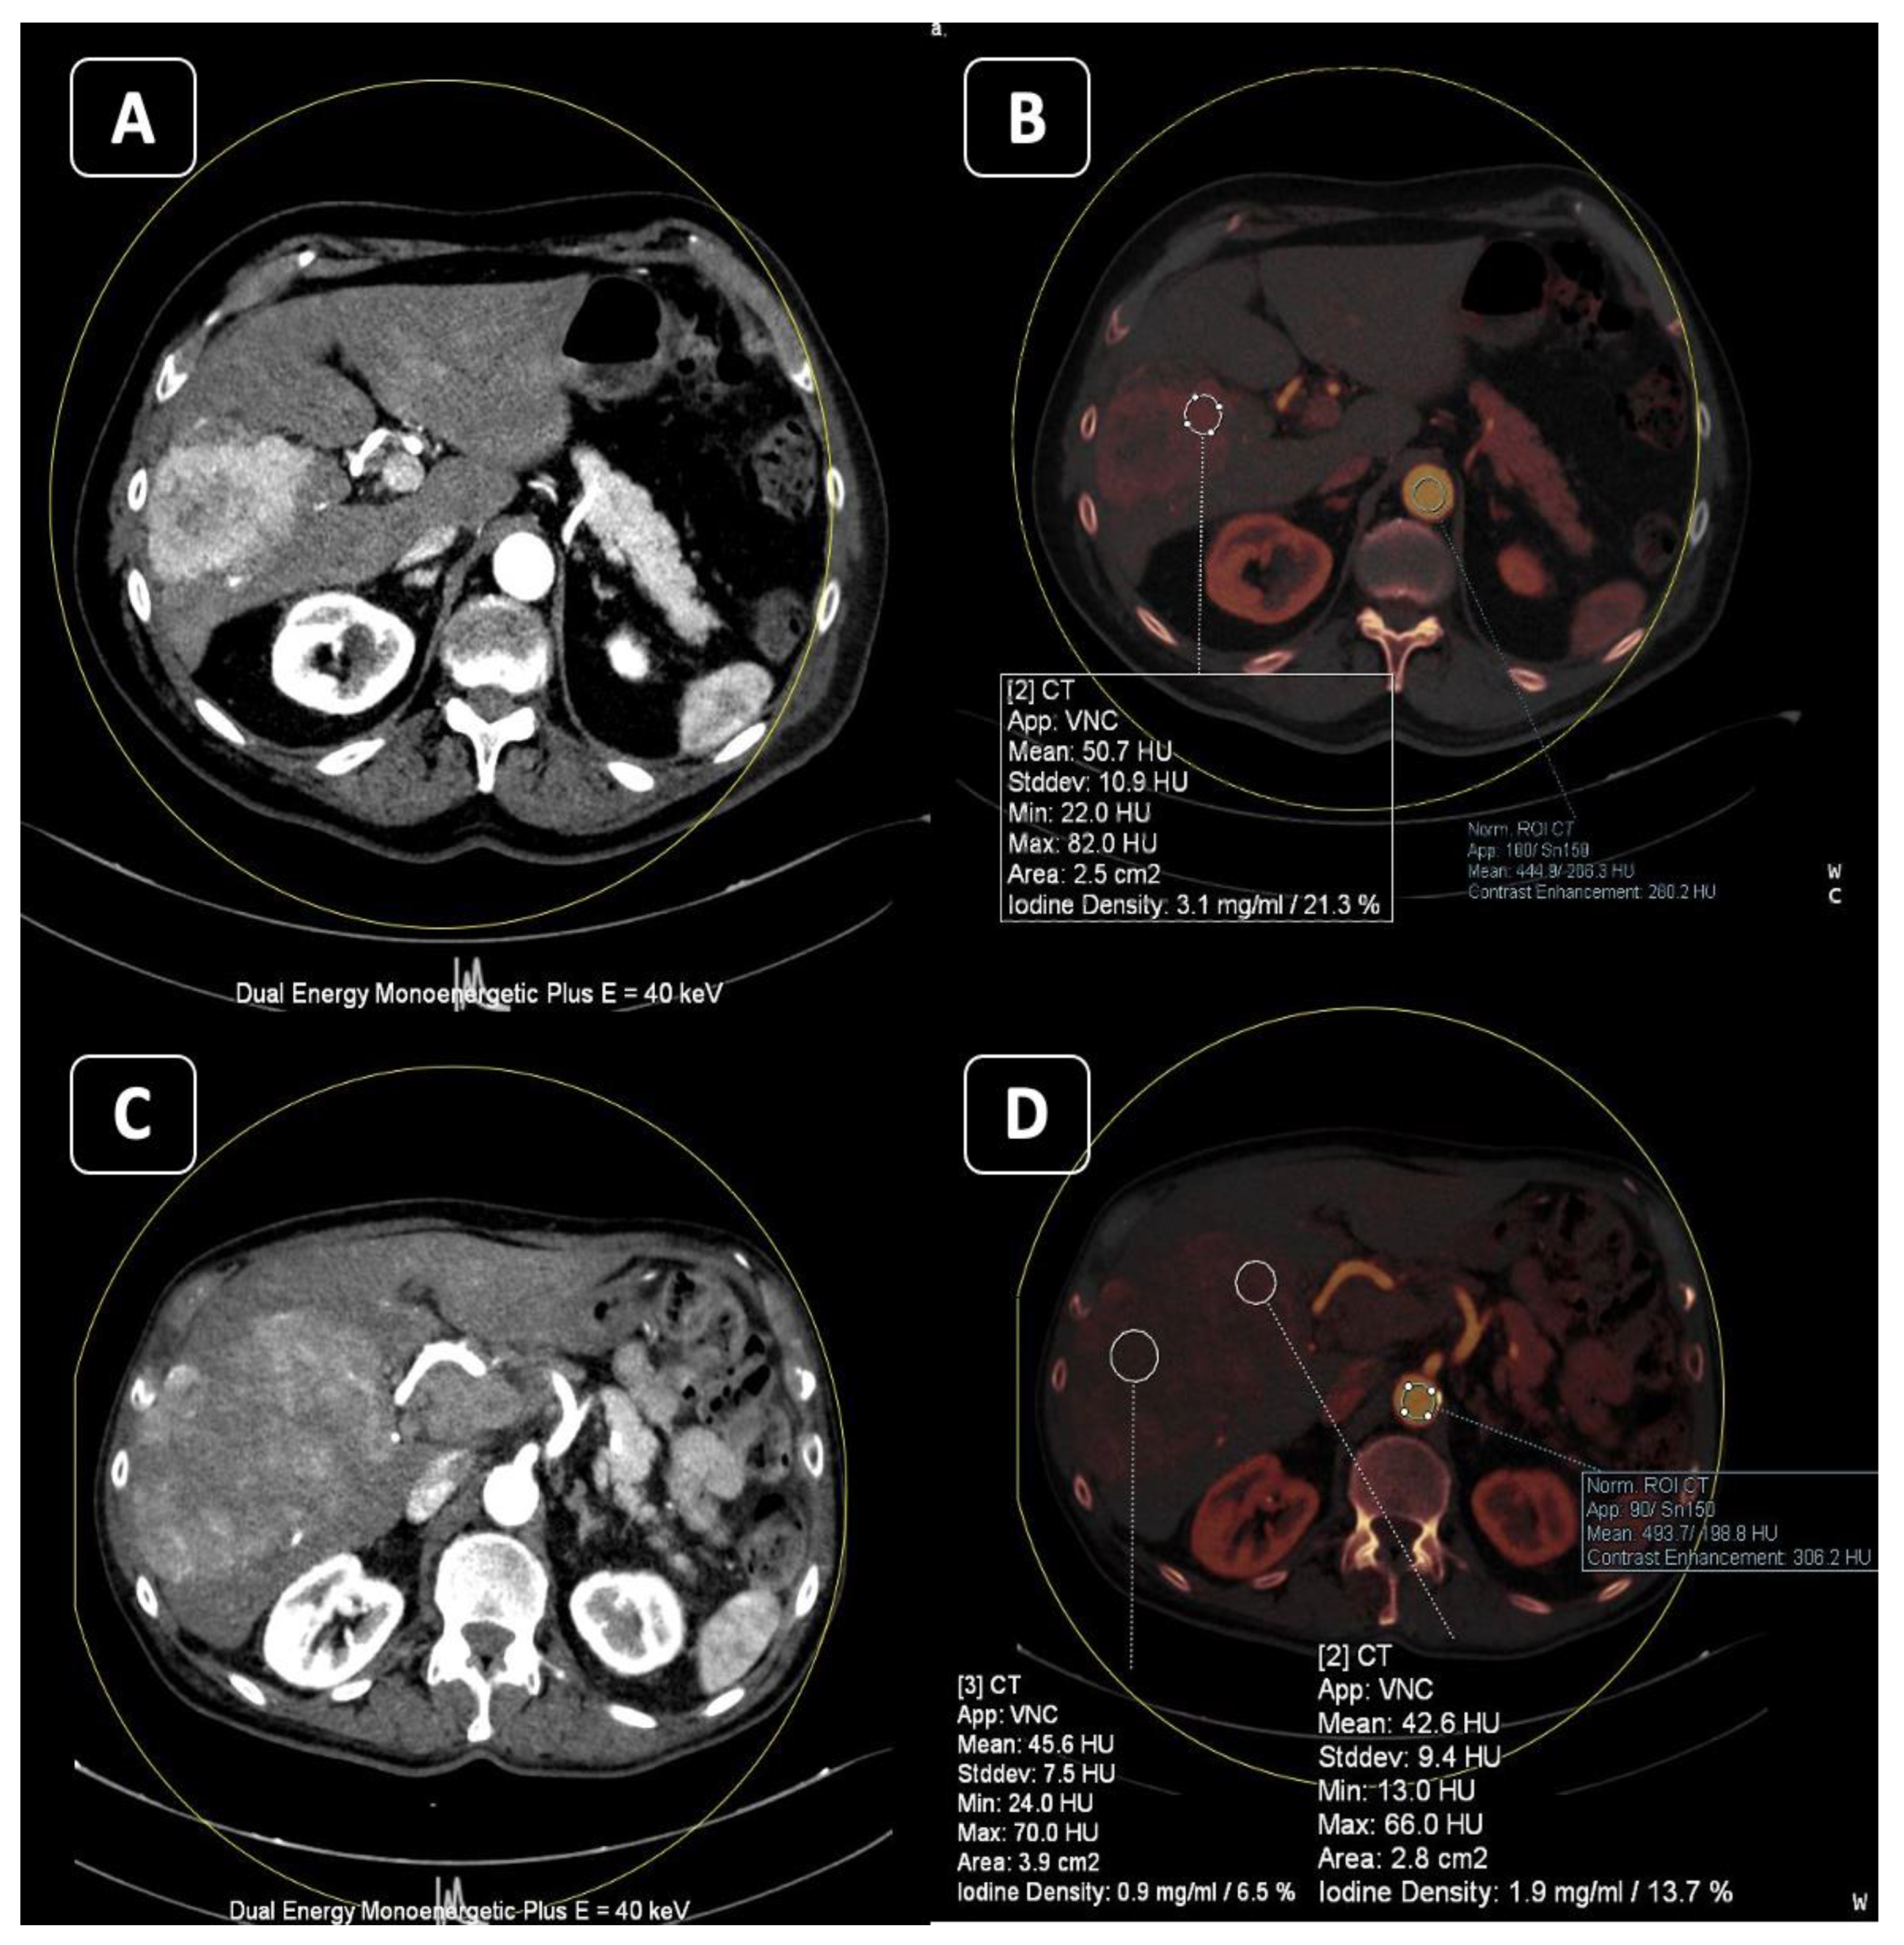

3. Iodine MAP

3.1. Applications